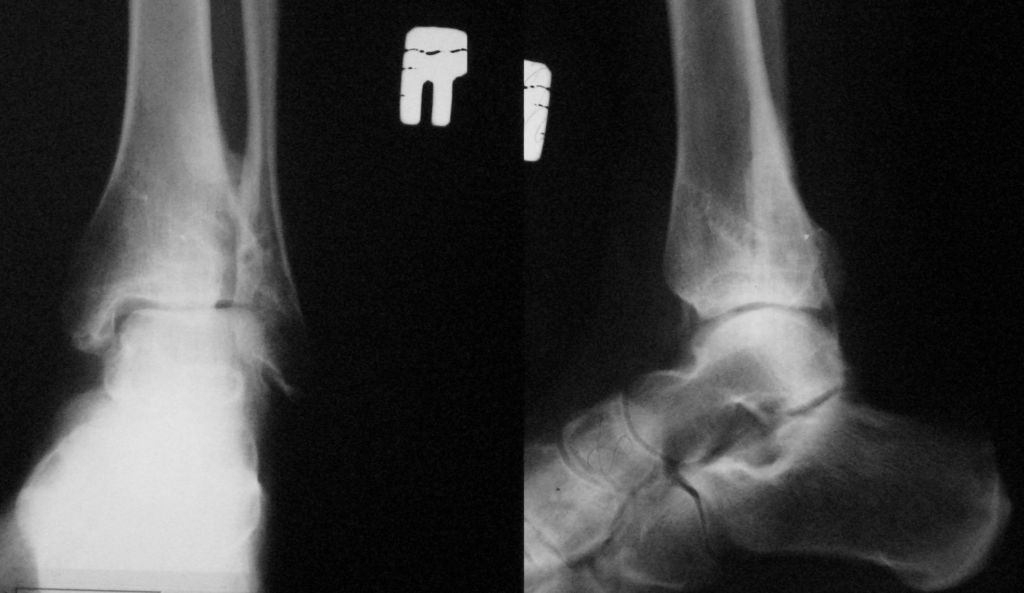

Здравствуйте уважаемые доктора!Прошу помочь определится с дальнейшей тактикой лечения.В январе была травма правого ГСС, "закрытыйпереломовывих правого ГСС с разрывом дистальногосиндесмоза, отрывом заднего края тибиа вывихомстопы наружу".

Проведен МОС лодыжек в одной из районных клиник. Наложен циркулярный гипс на три месяца. Послеоперационный период без осложнений, под наблюдением районного травматолога. Реабилитация - массаж, ЛФК. В октябре 2007 сняли конструкции. Примерно через 1 мес. появилась боль при нагрузках в районе нарухной лодыжки, незначительный отек, обычно после длительного хождения (2-3 часа). Обратился к оперировавшему доктору - сделал снимок (во вложении) сказал, есть небольшой подвывих стопы, что ничего страшного, продолжать разрабатывать сустав, назначил противовоспалительные мази. На вопрос о необходимости хирургической коррекции - ответил, ничего делать не надо. Мне 29 лет, искренне хочется сохранить сустав. Уважаемые специалисты, прошу помочь в моем случае. Если необходима какая-либо дополнительная информация (ранние снимки и проч.) - пожалуйста.